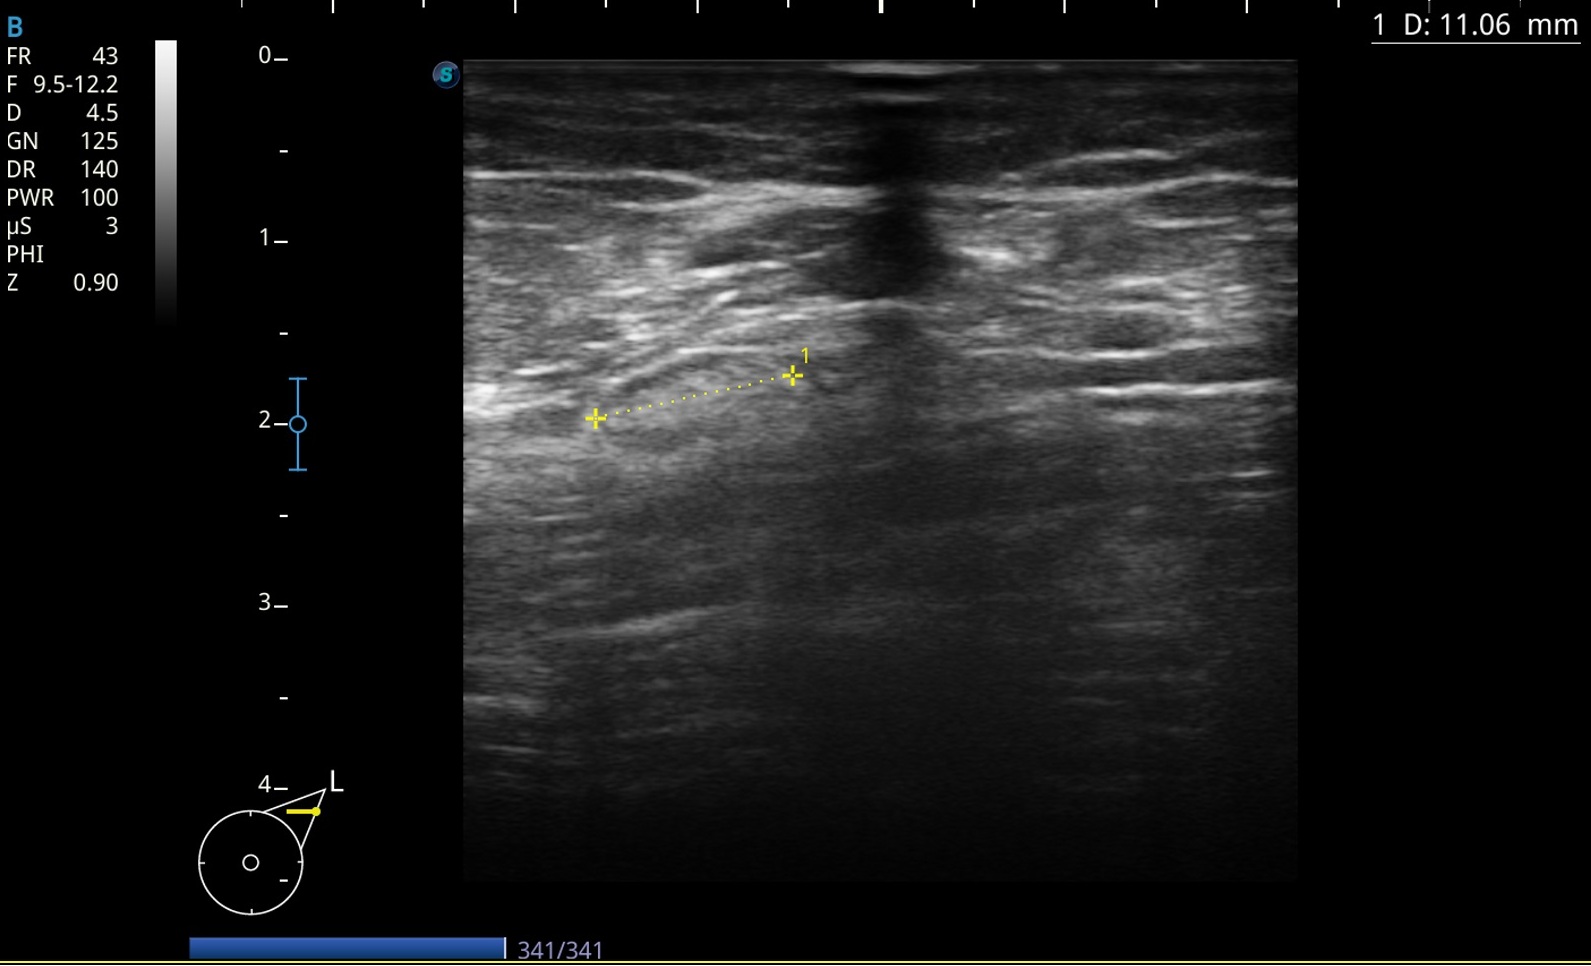

Adenopatía derecha de 1,2 cm de aspecto normal.

Adenopatía derecha redonda mal definida hipoecoica de 1,4 cm con vascularización central de aspecto patológico.